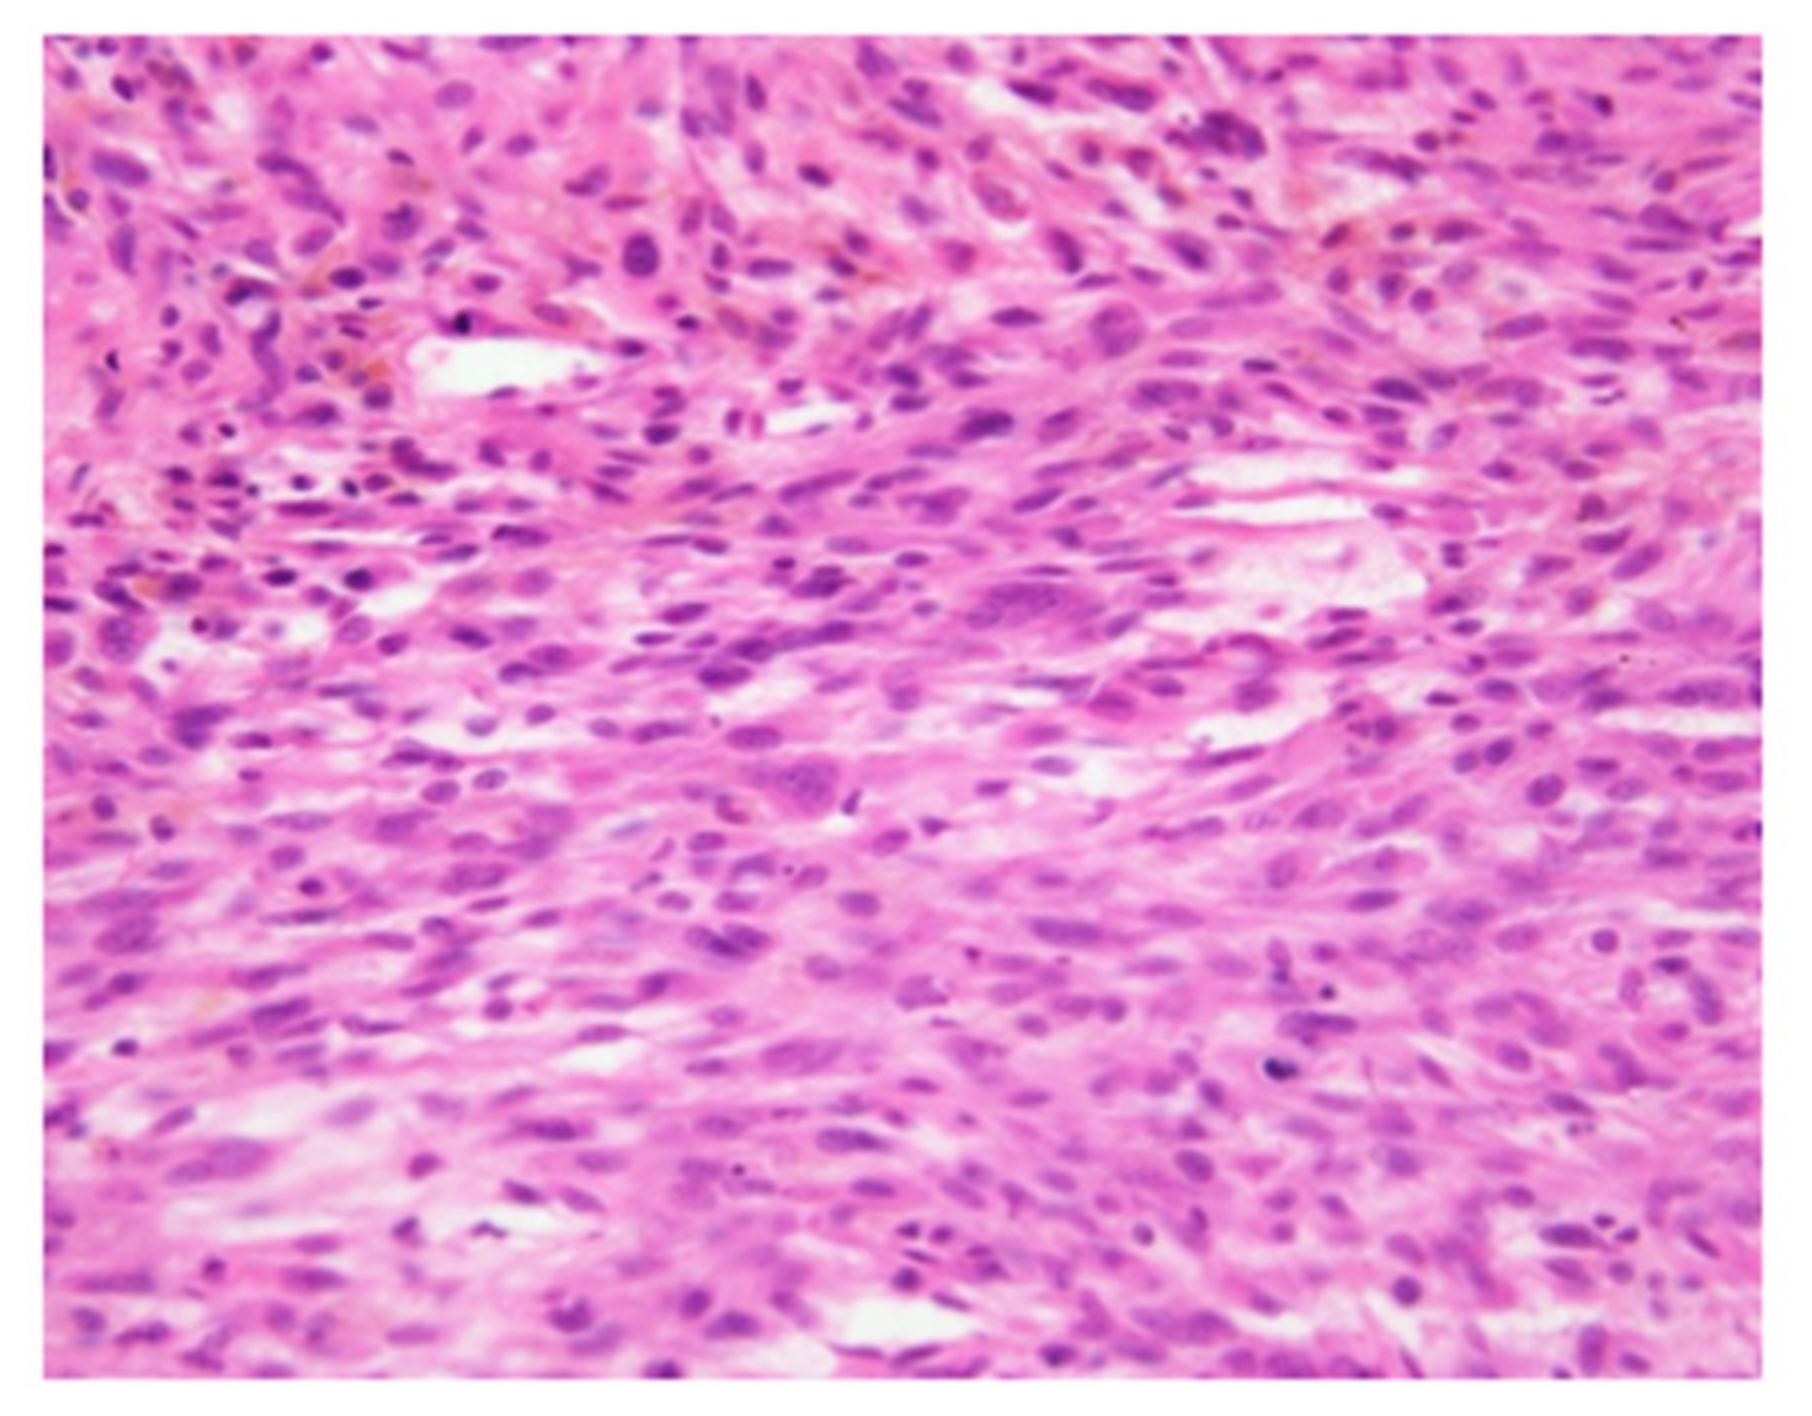

2. Case Presentation